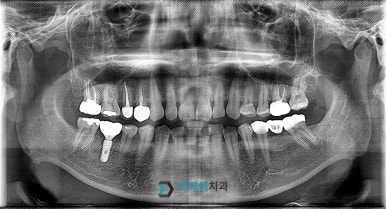

<전 2022-03-24>

<후 2022-07-01>